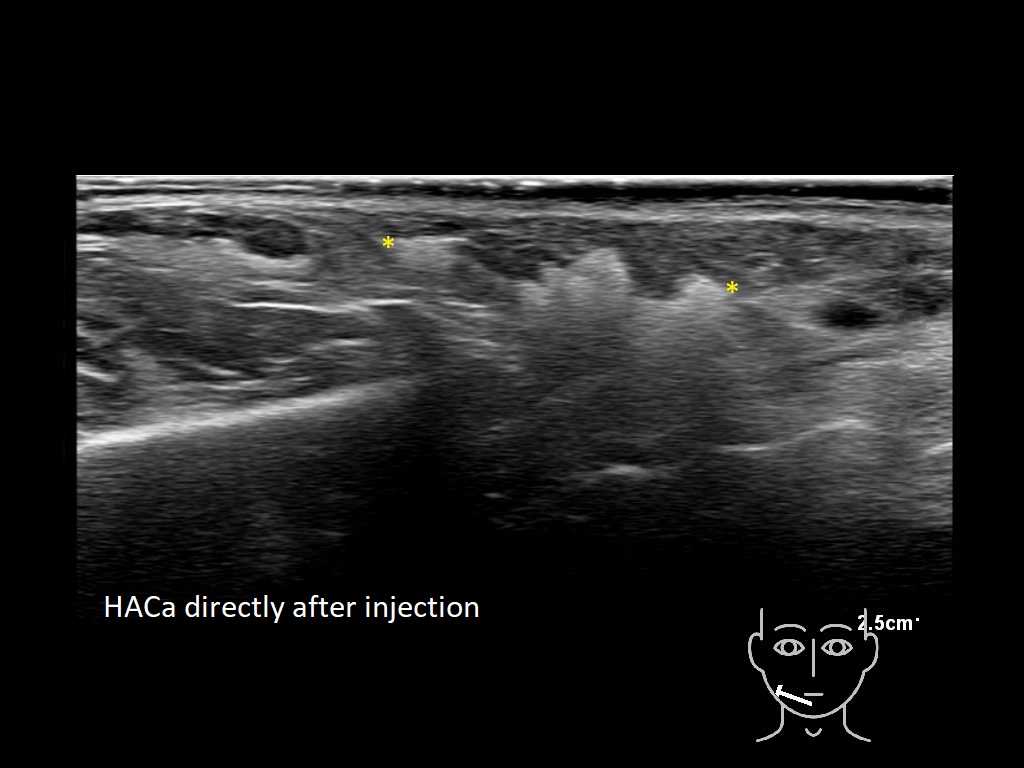

haca 0

HAca 10a